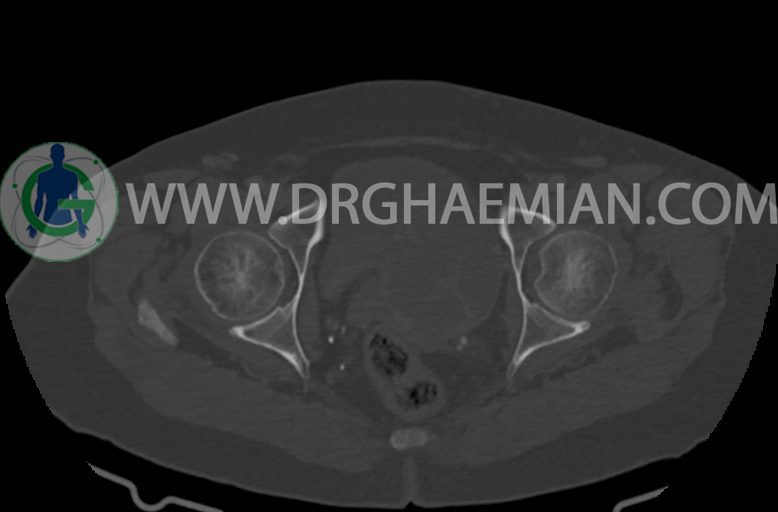

–ضایعه ی mass like هیپردنس- هتروژن به قطر 42mm در سمت راست لگن

–تغییرات DJD در L5/S1

مشهود است.